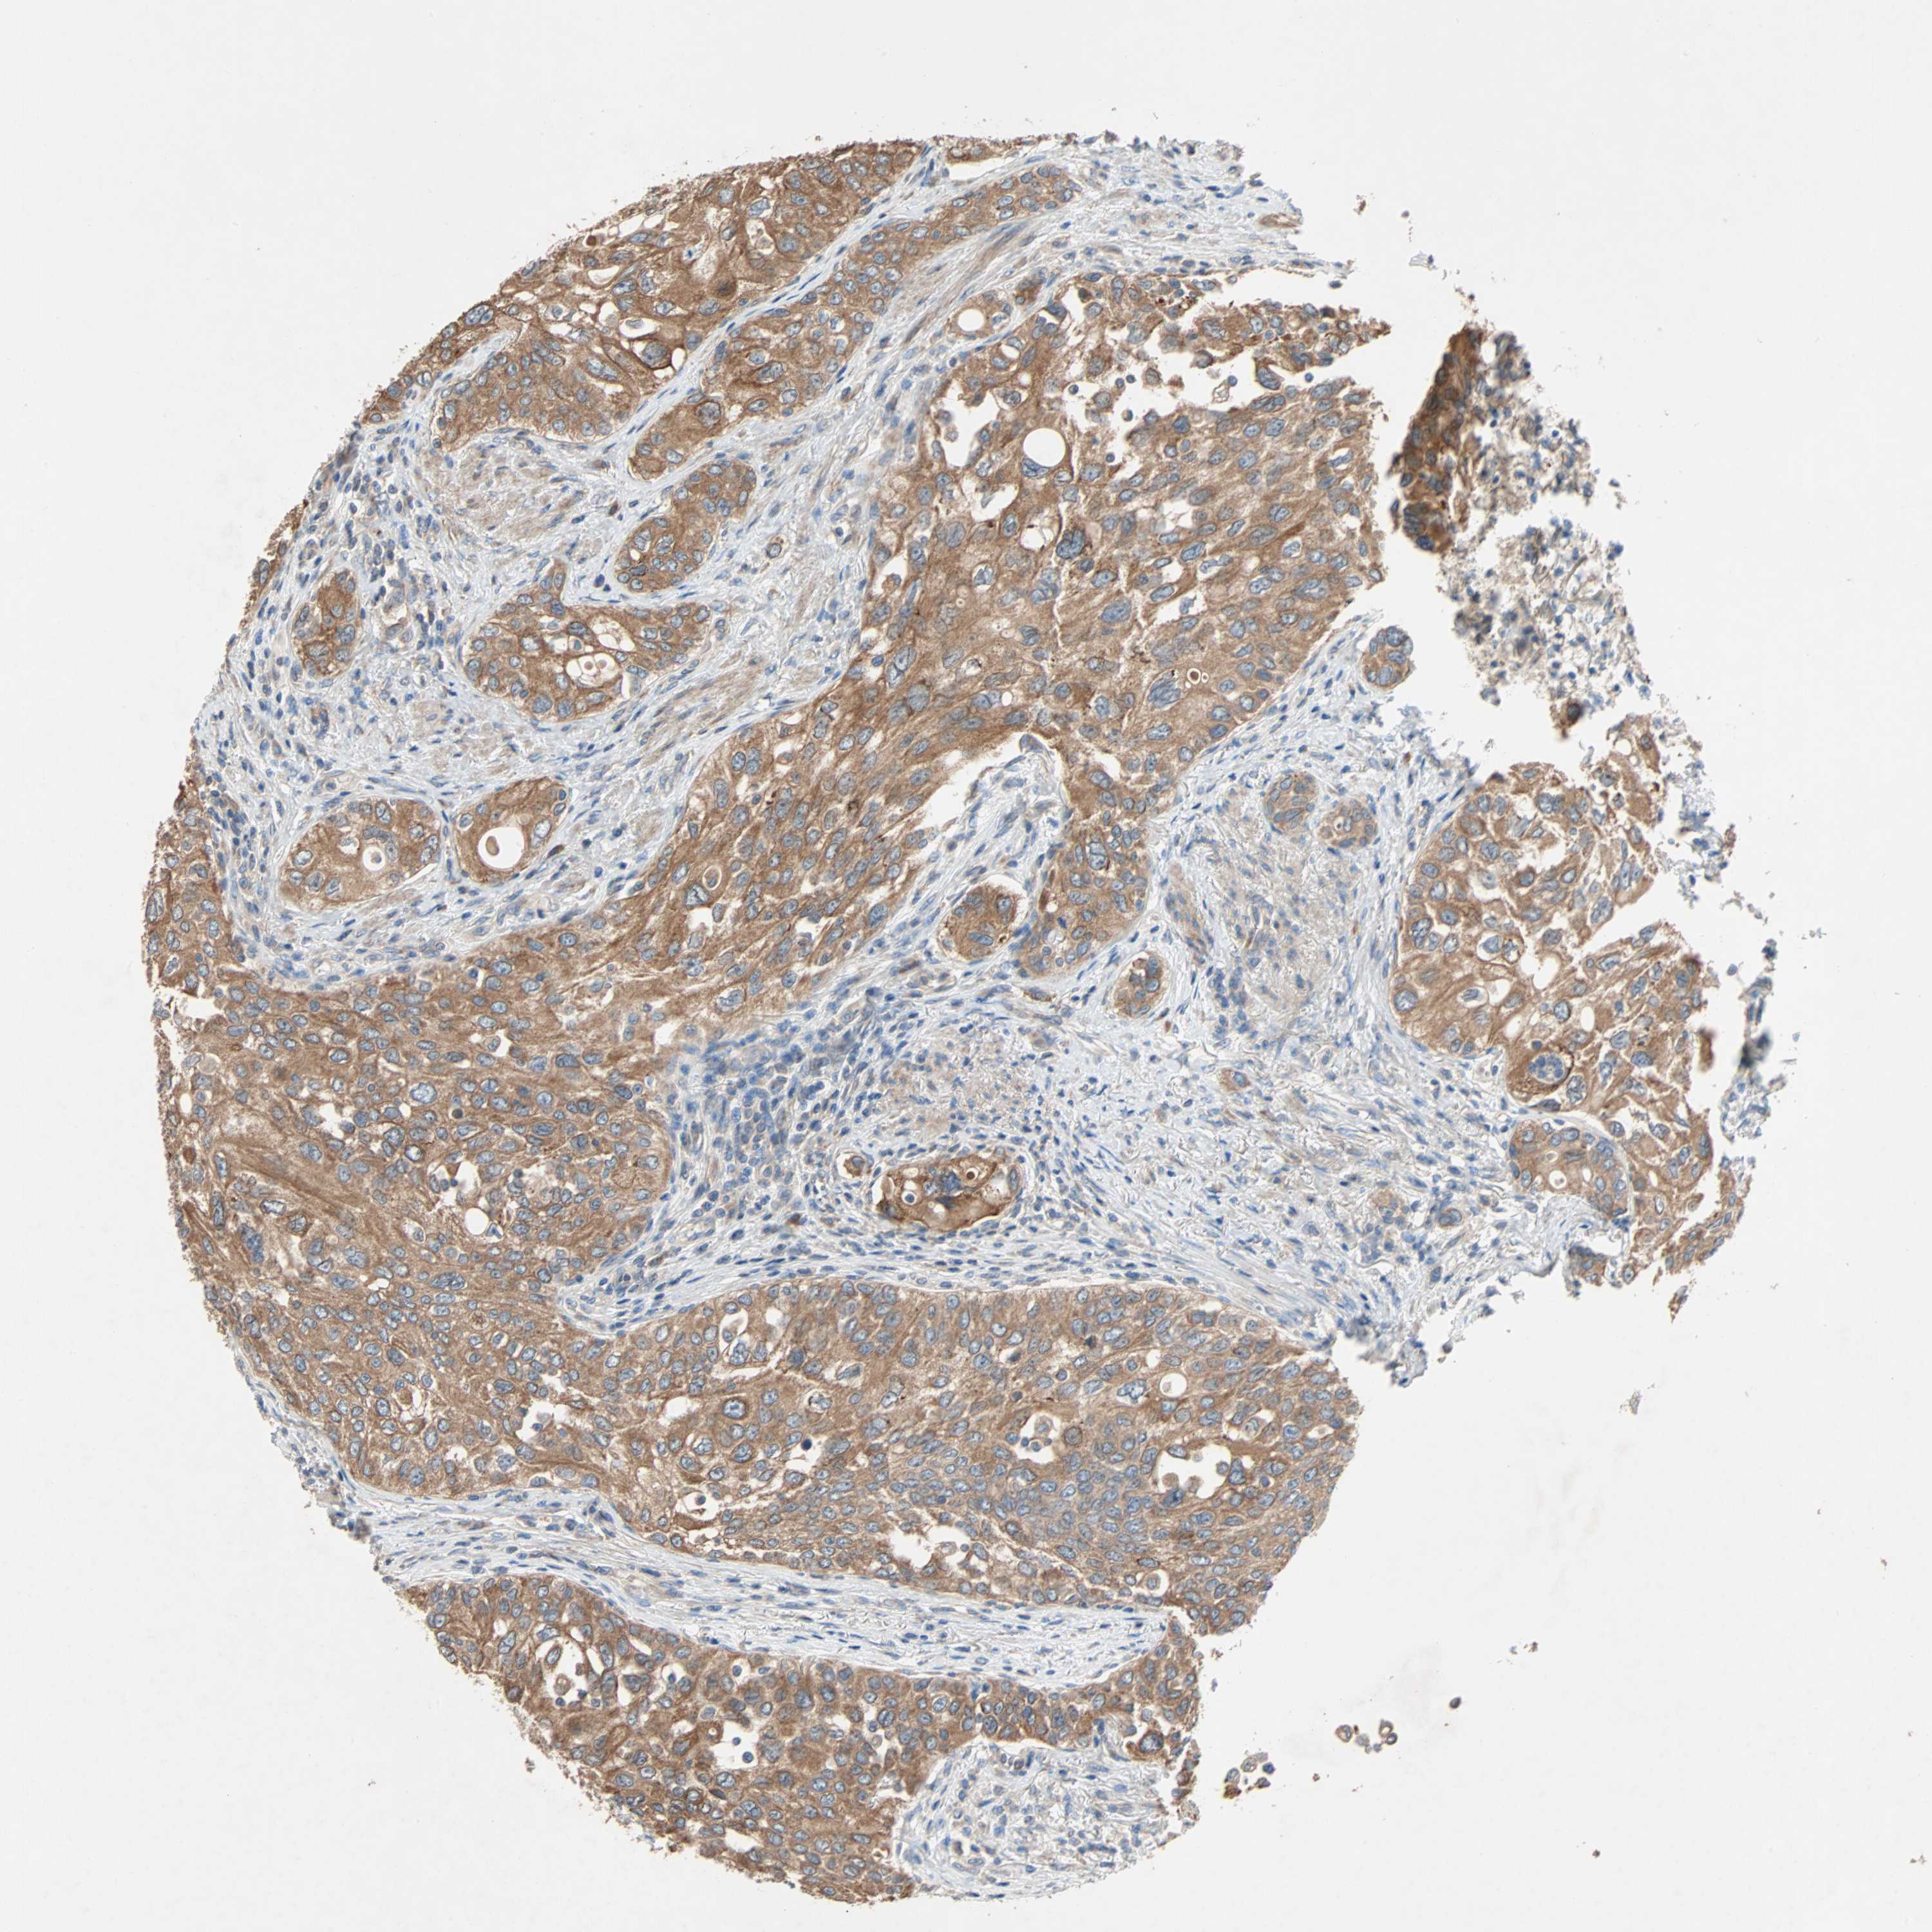

UROTHELIAL CANCER - Protein expressioni

A mouse-over function shows sample information and annotation data. Click on an image to view it in a full screen mode. Samples can be filtered based on level of antibody staining by selecting one or several of the following categories: high, medium, low and not detected. The assay and annotation is described here.

Note that samples used for immunohistochemistry by the Human Protein Atlas do not correspond to samples in the TCGA dataset.

Antibody stainingi

Antibody staining in the annotated cell types in the current human tissue is reported as not detected, low, medium, or high, based on conventional immunohistochemistry profiling in selected tissues. This score is based on the combination of the staining intensity and fraction of stained cells.

Each image is clickable and will lead to virtual microscopy that enables deeper exploration of all samples and also displays staining intensity scores, fraction scores and subcellular localization as well as patient and tissue information for each sample.

Antibody HPA007478

Antibody HPA007966

Urothelial carcinoma, Low grade

Urothelial carcinoma, High grade